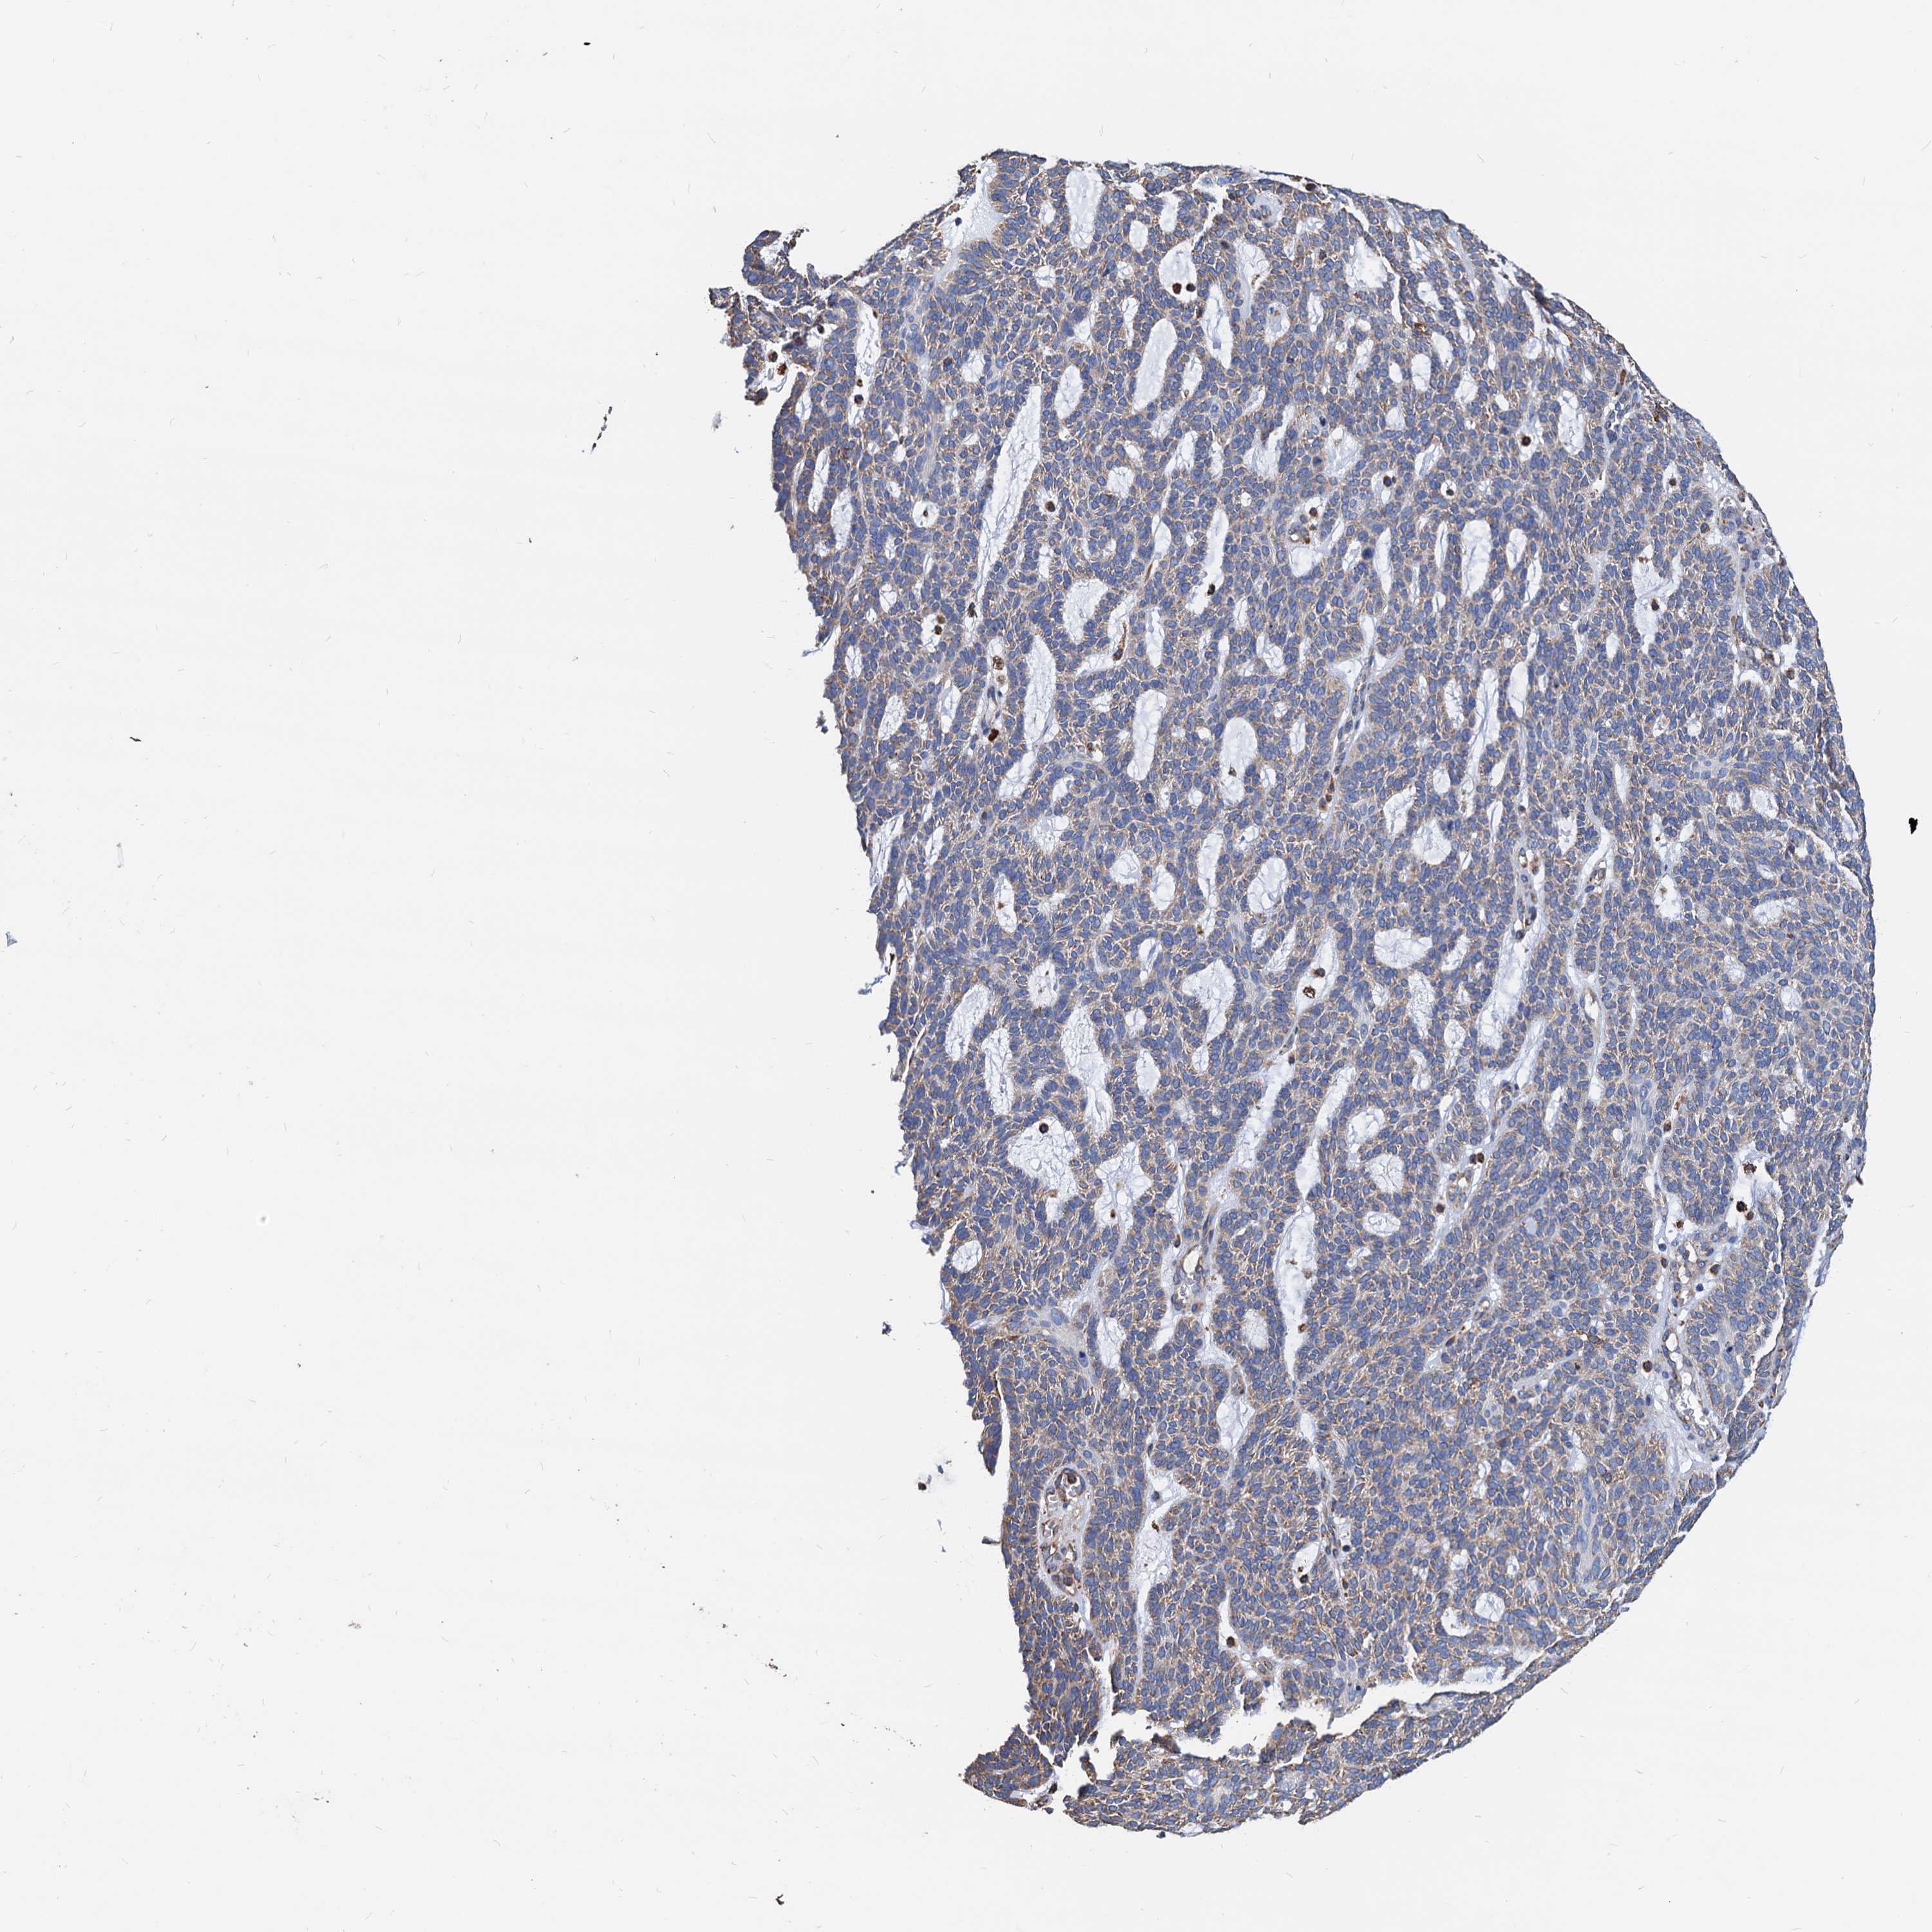

SKIN CANCER - Protein expressioni

A mouse-over function shows sample information and annotation data. Click on an image to view it in a full screen mode. Samples can be filtered based on level of antibody staining by selecting one or several of the following categories: high, medium, low and not detected. The assay and annotation is described here.

Each image is clickable and will lead to virtual microscopy that enables deeper exploration of all samples and also displays staining intensity scores, fraction scores and subcellular localization as well as patient and tissue information for each sample.

Antibody HPA038845

Antibody HPA038846

Antibody CAB005221

Staining

High

Medium

Low

Not detected

Intensity

Strong

Moderate

Weak

Negative

Quantity

>75%

75%-25%

<25%

None

Location

Nuclear

Cytoplasmic/membranous

Cytoplasmic/membranous,nuclear

Basal cell carcinoma

Squamous cell carcinoma, NOS

Squamous cell carcinoma, metastatic, NOS